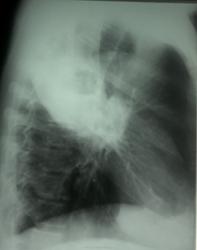

Контроль от 27.12.13

Выставил: Абсцедирующая пневмония в\доли правого легкого. Смущает отсутствие динамики.

Представлена динамика за 21 день. Наверное, для констатации динамики абсцесса придется подождать еще пару месяцев.